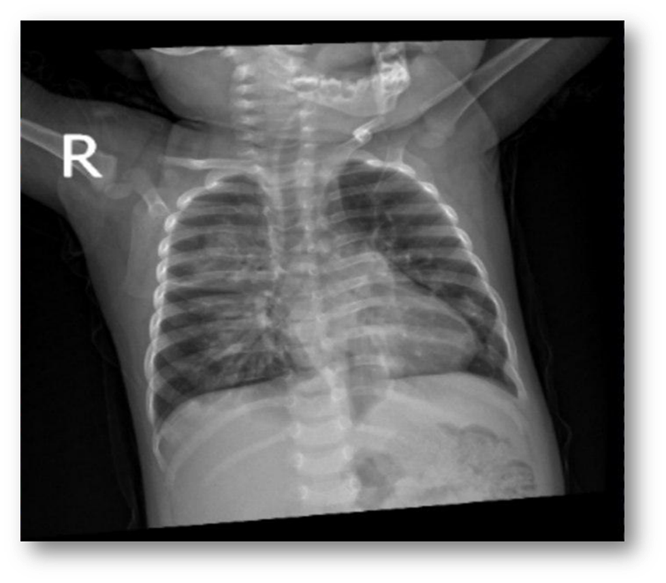

Chest x-ray:

Right lower lung zone nodular opacity. Conclusion > pneumonia